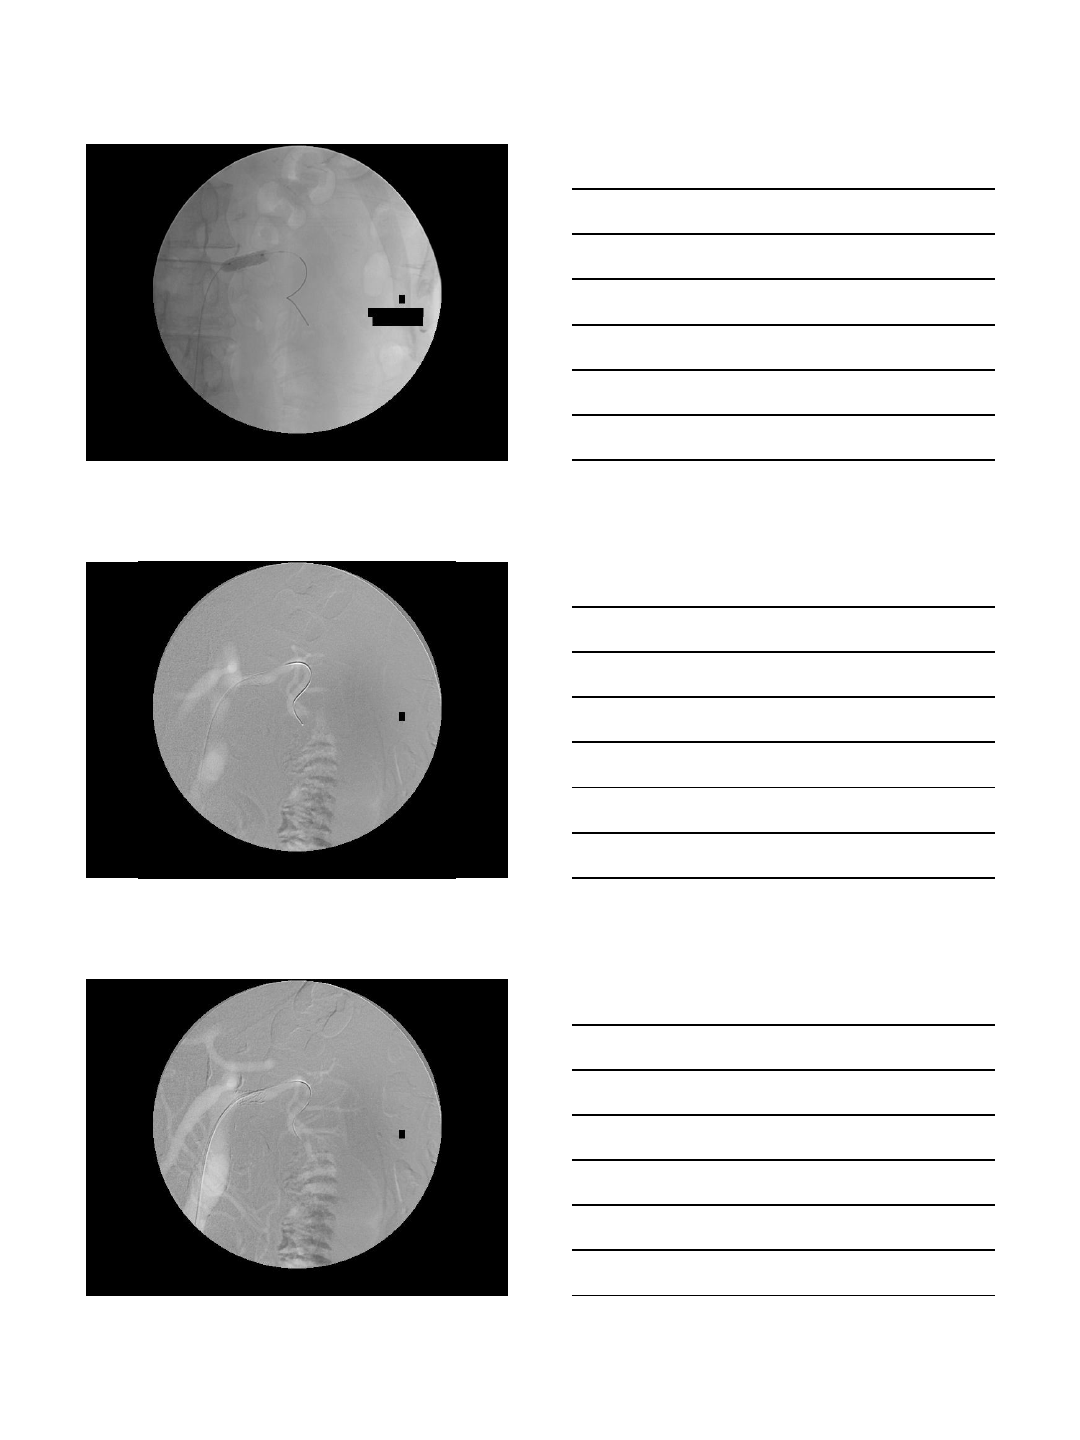

ANEURYSM REPAIR

Case Presentation

•78 year old man with severe atherosclerotic

disease, chronic renal failure with a stable

serum creatinine at 2.5 mg/dL and a large

iliac artery aneurysm

•Needs aneurysm repair but it is desirable to

CO2 arteriogram and embolization

•Iliac aneurysm coiling with CO2

•AAA stent-graft using CO2 & IVUS

•Total contrast used: 30 cc

•Renal function unchanged